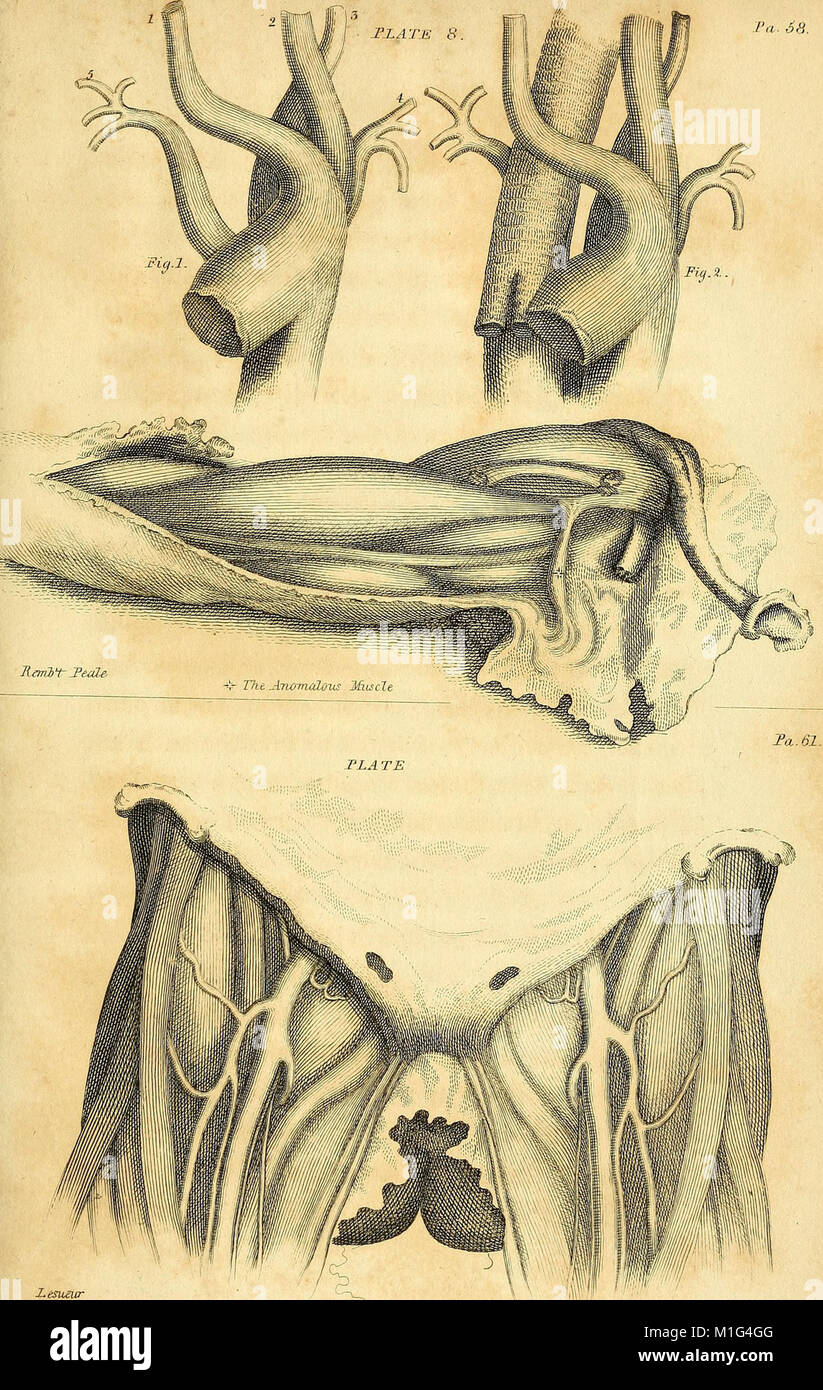

Anatomical investigations, comprising descriptions of various fasciae of the human body to which is added an account of some irregularities of structure and morbid anatomy; with a description of a new (18170837441) Stock Photohttps://www.alamy.com/image-license-details/?v=1https://www.alamy.com/stock-photo-anatomical-investigations-comprising-descriptions-of-various-fasciae-173073168.html

Anatomical investigations, comprising descriptions of various fasciae of the human body to which is added an account of some irregularities of structure and morbid anatomy; with a description of a new (18170837441) Stock Photohttps://www.alamy.com/image-license-details/?v=1https://www.alamy.com/stock-photo-anatomical-investigations-comprising-descriptions-of-various-fasciae-173073168.htmlRMM1G4GG–Anatomical investigations, comprising descriptions of various fasciae of the human body to which is added an account of some irregularities of structure and morbid anatomy; with a description of a new (18170837441)

'Anatomical Investigations' (1798) offers detailed descriptions of human fasciae, irregularities in body structure, and cases in morbid anatomy. It also introduces a new anatomical discovery, contributing to medical understanding of human anatomy. Stock Photohttps://www.alamy.com/image-license-details/?v=1https://www.alamy.com/stock-photo-anatomical-investigations-1798-offers-detailed-descriptions-of-human-173073134.html

'Anatomical Investigations' (1798) offers detailed descriptions of human fasciae, irregularities in body structure, and cases in morbid anatomy. It also introduces a new anatomical discovery, contributing to medical understanding of human anatomy. Stock Photohttps://www.alamy.com/image-license-details/?v=1https://www.alamy.com/stock-photo-anatomical-investigations-1798-offers-detailed-descriptions-of-human-173073134.htmlRMM1G4FA–'Anatomical Investigations' (1798) offers detailed descriptions of human fasciae, irregularities in body structure, and cases in morbid anatomy. It also introduces a new anatomical discovery, contributing to medical understanding of human anatomy.